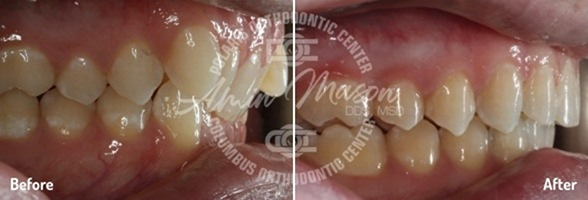

Case 6

A 23-year-old female patient presented to our office with severe crowding and worn teeth. The patient was not happy with the appearance of the teeth and the shape of the restoration on tooth #9. The patient was treated with extraction of 4 premolar teeth and the Damon system in 20 months. She will undergo whitening and restoration of tooth #9 for improved aesthetics.